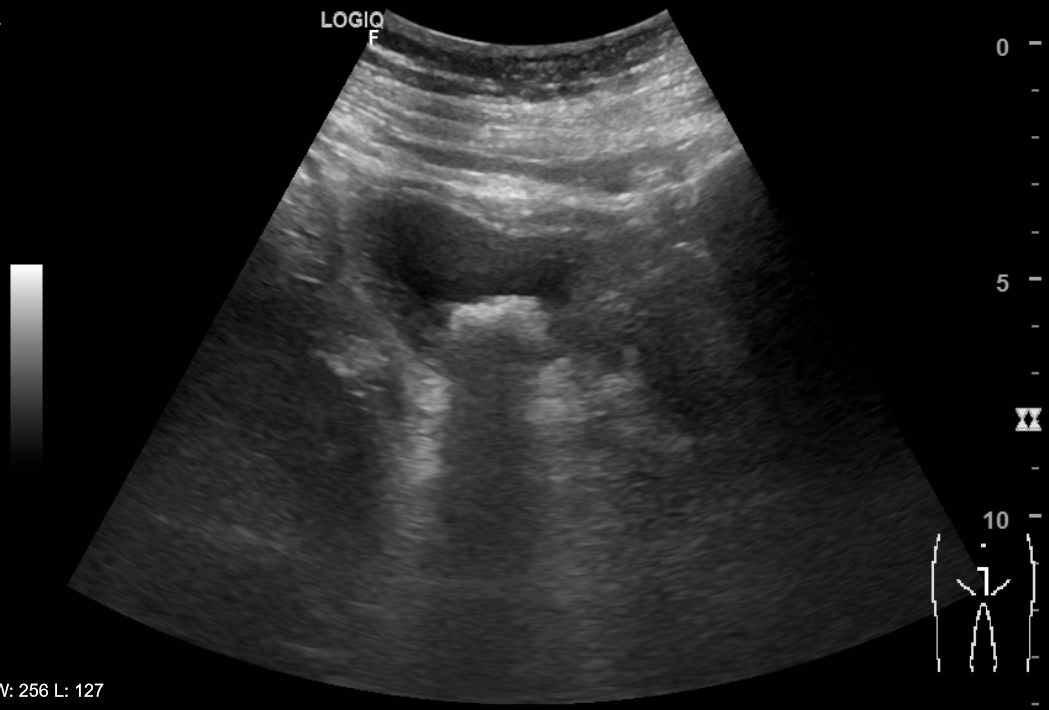

Riñones de morfología y tamaño normales. No se aprecian colecciones intrarrenales ni perirrenales. Sin ectasia de sistemas excretores. Quiste cortical simple en polo superior de riñón izquierdo de 6x6cm. Vejiga poco replecionada de paredes uniformemente engrosadas y trabeculadas. Múltiples imágenes hiperecogénicas con ausencia de registro Doppler y con sombra posterior que sugiere cistolitiasis. Próstata de aspecto normal con volumen de 21 cc. Volumen premiccional de 89 cc y posmiccional de 11 cc.

Juicio clínico: Litiasis en la vejiga. Diagnóstico diferencial: Tumor de vejiga/Hipertrofia benigna de próstata/Infección del trato urinario.